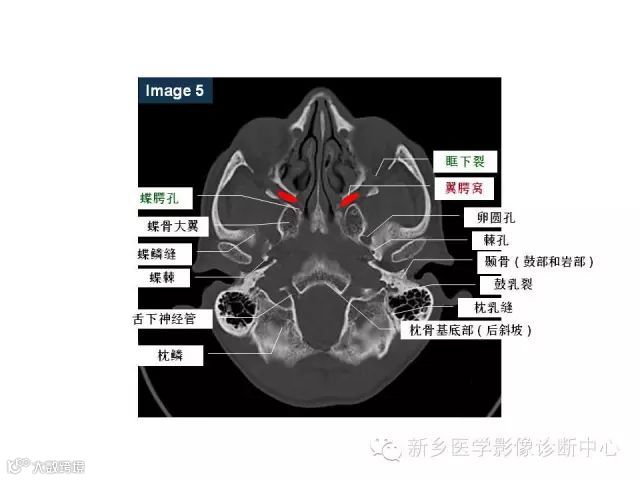

颅底孔道解剖详解

值得收藏!